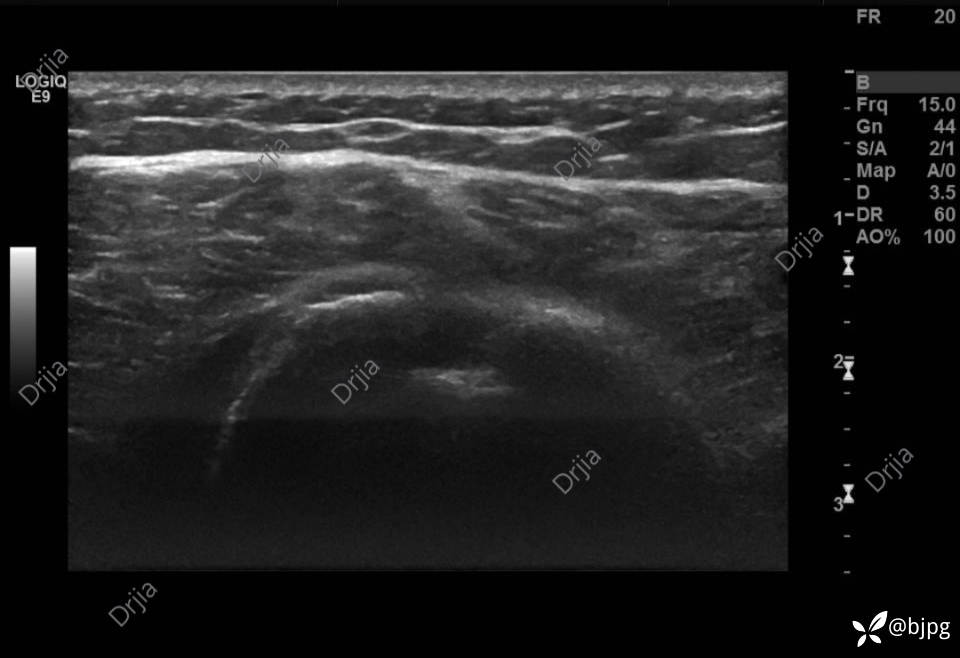

左侧结节间沟空虚